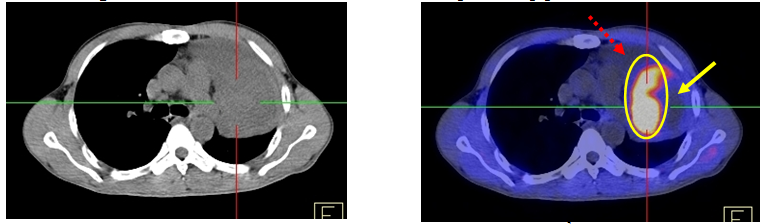

Ca lâm sàng 4: bệnh nhân nam, 63 tuổi, chẩn đoán Ung thư phổi (qua nội soi phế quản phát hiện ra u, giải phẫu bệnh là ung thư biểu mô vảy).

Hình 4: Trường hợp một bệnh nhân không xác định được GTV trên CT, nhờ PET/CT xác định được BTV.

Ca lâm sàng 5: bệnh nhân nam, 53 tuổi, chẩn đoán Ung thư phổi (giải phẫu bệnh: ung thư biểu mô vảy).

Ca lâm sàng 6: bệnh nhân nam, 52 tuổi, chẩn đoán: U phổi/ Xẹp phổi

Hình 6. Trên CT thông thường không phân biệt được rõ ràng tổ chức u, vùng xẹp phổi. Trên hình PET/CT giúp phân biệt rõ tổ chức u (vùng sáng màu), vùng xẹp phổi (mũi tên đứt nét) và vùng hoại tử (mũi tên liền), chỉ điểm cho việc sinh thiết u làm giải phẫu bệnh cũng như xác định thể tích đích trong lập kế hoạch xạ trị.